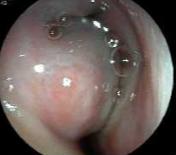

分泌性中耳炎有哪些表现?鼓膜完整得,但是呈现琥珀色,部分可以看到液平。